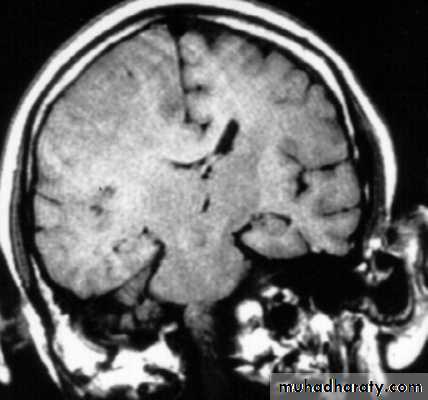

Copper-beating’ marking

Skull X-ray findings in increased intracranial pressure

• Sutural separation in children.

• ‘Copper-beating’ marking of the cranial vault.

• Thinning of dorsum sellae.

• Erosion of the posterior clinoid process.